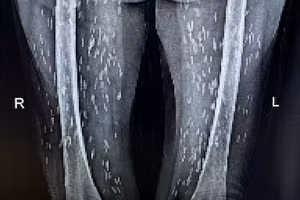

Rùng mình hình ảnh kén sán dày đặc trên người bệnh nhân 18/10/2022 22:55 GD&TĐ - Bệnh nhân 74 tuổi người Vĩnh Tường, Vĩnh Phúc được bác sĩ Bệnh viện Hữu nghị Lạc Việt chẩn đoán nhiễm kén sán dây lợn.